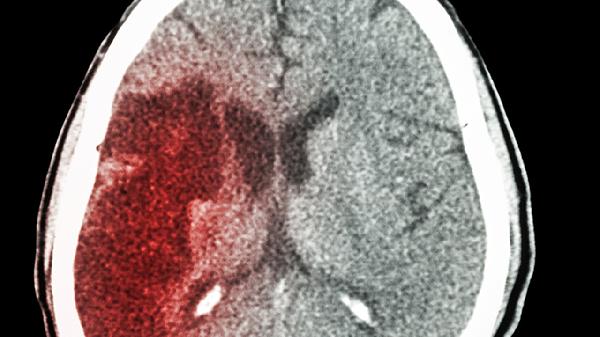

分流管堵塞或移位是常见并发症,可能引起脑室再度扩大。患者会出现呕吐、嗜睡等颅高压症状,需通过CT检查确认分流管状态,必要时手术调整或更换分流装置。